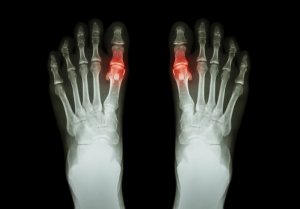

Jicht is een aandoening die wordt veroorzaakt door de opeenhoping van microscopisch kleine kristallen van urinezuur in de gewrichten. Deze kristallen vormen kleine bultjes onder de huid of worden afgezet in de urinewegen.

Wanneer dit uitscheidingsproces echter niet voldoende is, stijgen de urinezuurspiegels tot abnormale waarden. Kristallen worden gevormd en deze worden afgezet in de gewrichten, waardoor er periodes met scherpe pijn optreden.

- Meestal is het aangetaste gewricht warm en rood (ontstoken). Over het algemeen is het ook gevoelig en opgezwollen.

Aan de andere kant kunnen sommige mensen chronische jicht ontwikkelen. Dit kan leiden tot beschadiging van één of meerdere gewrichten. Deze beschadigingen kunnen vervolgens leiden tot verlies van mobiliteit in bepaalde gewrichten.